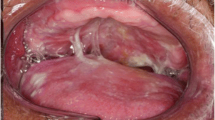

Oral Mucosa-Sparing IMRT

Within the oral mucosa (OM) are 600–1,000 minor SGs, and until recently there was no option to spare them; also the clinical relevance of these secretions was unclear. Despite contributing <10 % WMS they contribute the majority of mucins [50] which are associated with mucosal moisture retention and xerostomia at rest and at night.

The dosimetric and clinical benefits of IMRT for OM sparing, when compared to 3D-CRT, have been shown in a planning study of oropharyngeal carcinoma patients [55]. IMRT provides a reduction in the maximum OM dose, defined as the OM outside the target tumour volume, but significantly this is only possible when a dose constraint is applied to the OM. In this study a clinically relevant maximum OM dose was defined as 30 Gy (2 Gy per fraction, 6 weeks) to the spared region. When IMRT treatment was replanned for the same patient with no dose constraint applied, a significantly increased dose to the OM was seen, with significantly larger volume of OM receiving ≤39.3 Gy vs. 3D-CRT. This study also reported clinical correlation in 19 IMRT-treated patients by comparing RTOG acute mucositis score, in the spared region of the OM with the region within the PTV. This was significantly reduced from week 2 of treatment onwards (p < 0.01) compared to the unspared regions. Though not reporting on minor SG function or xerostomia, it is promising that OM may be spared with no significant impact on PG mean dose, target volume coverage or increase in other OAR doses.